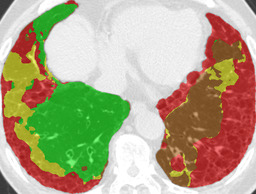

Recall, precision, and dice coefficient (a.k.a F-measure) were used for the evaluation. For the sake of the evaluation, continuous softmax outputs were converted into discrete class labels by selecting the classes that gave the maximum probability. Table 2 shows the evaluated metrics for each method. By paired t-tests, statistically significant differences were confirmed between the proposed method (λ=0.1𝜆0.1\lambda=0.1) and other methods in dice coefficients. As shown in Table 2, utilizing weakly annotated pixels increased precision and λ=0.1𝜆0.1\lambda=0.1 was the optimal value that balances recall and precision in this experiment. Evaluated dice coefficients for the proposed method (λ=0.1𝜆0.1\lambda=0.1) are shown in Figure 2. As shown in Figure 2, even though the proposed method improved the segmentation accuracy, segmentation accuracy varies between slices. Figure 3 shows the confusion matrix of the pixel-wise classification result. In Figure 3, Lweaksubscript𝐿𝑤𝑒𝑎𝑘L_{weak} pixels misclassified as corresponding Lstrongsubscript𝐿𝑠𝑡𝑟𝑜𝑛𝑔L_{strong} (e.g. pixels of lCON¯subscript𝑙¯𝐶𝑂𝑁l_{\overline{CON}} classified as lCONsubscript𝑙𝐶𝑂𝑁l_{CON}) are represented as “Others”. As shown in Figure 3, DLD class combinations with similar texture patterns such as HCM and EMP were misclassified into each other. Figure 4 shows the average result for each DLD class and tested method.

Ground truth Supervised only Proposed (λ=0.1𝜆0.1\lambda=0.1) Proposed (λ=1𝜆1\lambda=1)

CON \blacksquare

Refer to caption Refer to caption Refer to caption Refer to caption

0.839 0.868 0.824

GGO \blacksquare

0.693 0.676 0.876

HCM \blacksquare

0.581 0.770 0.435

EMP \blacksquare

0.793 0.847 0.815

NOR \blacksquare

0.978 0.968 0.974

Figure 4: Average results and dice coefficients for each DLD pattern. Automated segmentation results are superimposed with colors. For each DLD pattern, the slice that gave the median dice coefficient for the proposed method with λ=0.1𝜆0.1\lambda=0.1 was chosen to represent the average result. Note that although CNN performed multi-class segmentation, only one DLD pattern per slice was taken into account for the evaluation.